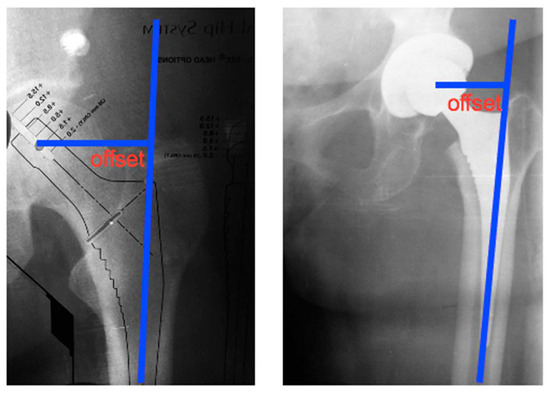

Figure 4.

Offset of the femoral component; distance from the center of the femoral head to the axis line of the distal part of the rod. [14] © MDPI 2023.

However, it must be emphasized that this idealized low-wear performance is not an inherent property of ceramic–ceramic bearings, but rather a systemic outcome maintained by a series of boundary conditions. For instance, if the inclination angle and forward tilt angle of the acetabular cup deviate from the recognized “safe zone,” the contact patch will shift from the center of the ball cap to its upper edge. As shown in Figure 4, this causes a sharp increase in contact stress and weakens the lubricating film thickness, transforming the interface from its original EHL state to mixed lubrication or even boundary lubrication. Furthermore, alterations in synovial fluid composition—such as reduced protein concentration or decreased viscosity—can diminish film thickness, thereby increasing friction heat and fatigue stress in microcontact zones. Research also indicates that even trace amounts of third-body particles entering the ceramic interface can elevate wear rates by an order of magnitude, as ceramics exhibit extreme sensitivity to hard particles—a characteristic markedly different from polyethylene. More critically, during transient high-load gait events like rapid pivoting or stair descent, impact force peaks often exceed those in routine simulation conditions. This abruptly subjects the previously stable interface to high stress zones, disrupting the lubricating film and triggering transient dry friction events [67].